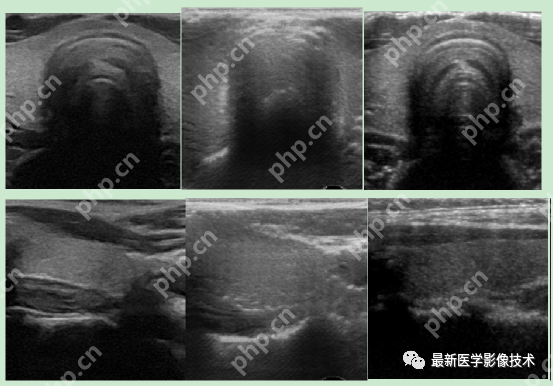

5、验证集部分生成结果

左图为低质量图像,中间为生成的高质量图像,右图为真实的高质量图像。